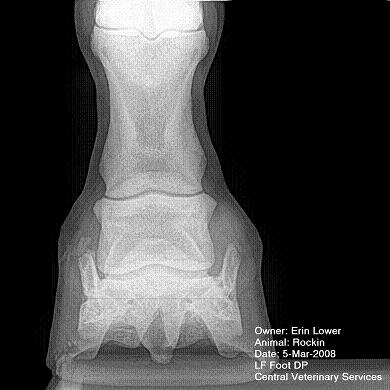

So, Rockin's x-rays were sent to a radiologist and he confirmed "normal" changes in the navicular bones for a horse her age, but slightly more significant ones in the right (sore) foot.

She also has sidebone in both fronts, but apparently that isn't causing any discomfort.

Finally, she has a "small chronic exostosis on the lateral aspect of the proximal phalanx" which, according to the radiologist, shouldn't be causing discomfort but I have read that these can be mild-to-moderately painful... I wouldn't mind another opinion on that.

I will attach as many images as possible from her x-rays (there are many different views). I don't have any pics of the feet as someone deleted them from my camera before I could download them. I'll try to take pics next time she is trimmed. Please, anyone with knowledge of hooves, give any opinions that you might have (especially Dr. O!)

I cannot rule out lesions based on these images but I will take your radiologist's word that he does not see significant lesions. The exostosis on the RF would be above the level of a well conducted PDN which I believed blocked the lameness before?

DrO